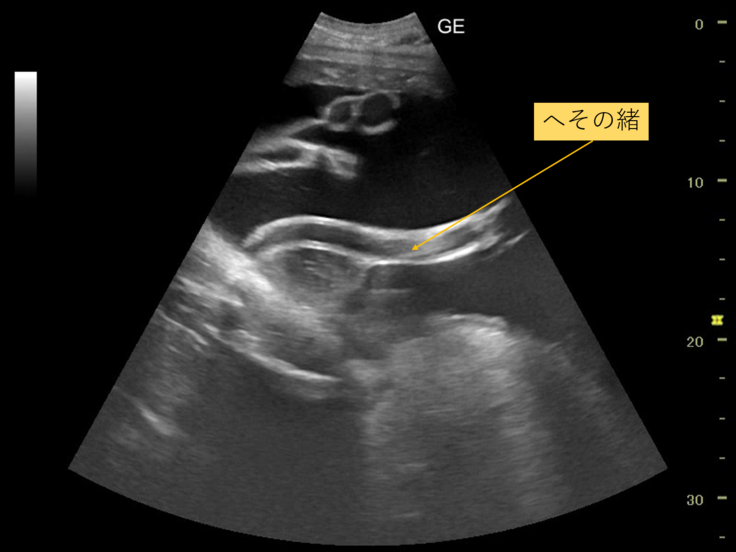

肝心の検査結果ですが、今回の検査では、胎児は超音波で見える範囲でじっとしてくれず、様子をはっきりと見ることはできませんでした。

ですが、へその緒の様子は確認できました。